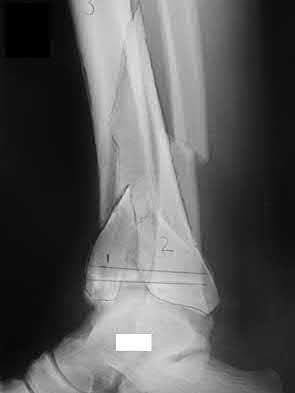

Figure A shows a patient after an open reduction and internal fixation of a bimalleolar ankle fracture.

Egol et al showed that by nine weeks, the total braking time of patients who had undergone fixation of a displaced right ankle fracture returns to the normal, baseline value.

Egol et al, also found that appropriate braking time returns at a point 6 weeks after initiation of weightbearing after treatment of lower extremity long bone and periarticular fractures, as examined with a driving simulator. No differences were seen in return of braking time between periarticular fractures and long bone injuries.